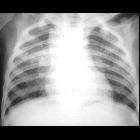

Toddler with

fever. CXR AP shows innumerable small pulmonary nodules that are uniformly distributed throughout the lungs.The diagnosis was miliary tuberculosis pneumonia.

Miliary tuberculosis is an uncommon pulmonary manifestation of tuberculosis. It represents haematogenous dissemination of uncontrolled tuberculous infection and carries a relatively poor prognosis. It is seen both in primary and post-primary tuberculosis and may be associated with tuberculous infection in numerous other tissues and organs.

Miliary deposits appear as 1-3 mm diameter nodules, which are uniform in size and uniformly distributed.